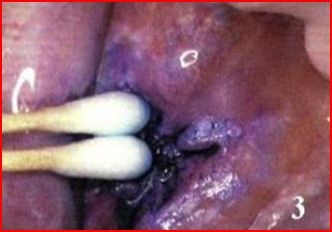

Chemiluminescence by definition is the emission of light from a chemical reaction [23]. Vizilite, a diagnostic tool for the early detection of oral cancer is based on the principle of chemiluminescence [fig. 3]. The kit contains 1% acetic acid solution, a capsule with an outer shell of flexible plastic and an inner vial of fragile glass, and a retractor [22]. Activation requires breakage of the glass vial by bending the capsule. This permits the chemical products to react and produce a bluish-white light with a wave length of 430-580 nm that lasts for around 10 min [24]. The procedure involves a one-minute mouthwash with 1% acetic acid solution. Under diffuse bluish-white chemiluminescent light, normal mucosa absorbs the light and appears blue, whereas the light is reflected by abnormal cells with a higher nucleus: cytoplasm ratio and by epithelium with excessive keratinization, hyperparakeratinization, and / or significant inflammatory infiltrate, which appear acetowhite with brighter, more marked, and more distinguishable borders [25-27]. ViziLite® system enhances the clinician’s ability to detect oral lesions, particularly white lesions and those with white and red areas. The sharp borders between normal and abnormal oral mucosa is easily delineated by ViziLite plus. Also, the borders observed usually extended beyond than those detected in the visual examination [8, 27]. The majority of these lesions can be diagnosed with incandescent light, and that mouthwash with acetic acid allowed the additional detection of some lesions [25]. The reported sensitivity is 100% and the specificity ranges from 0%-14.2%.

Fig. 3: Chemiluminescence with vizilite